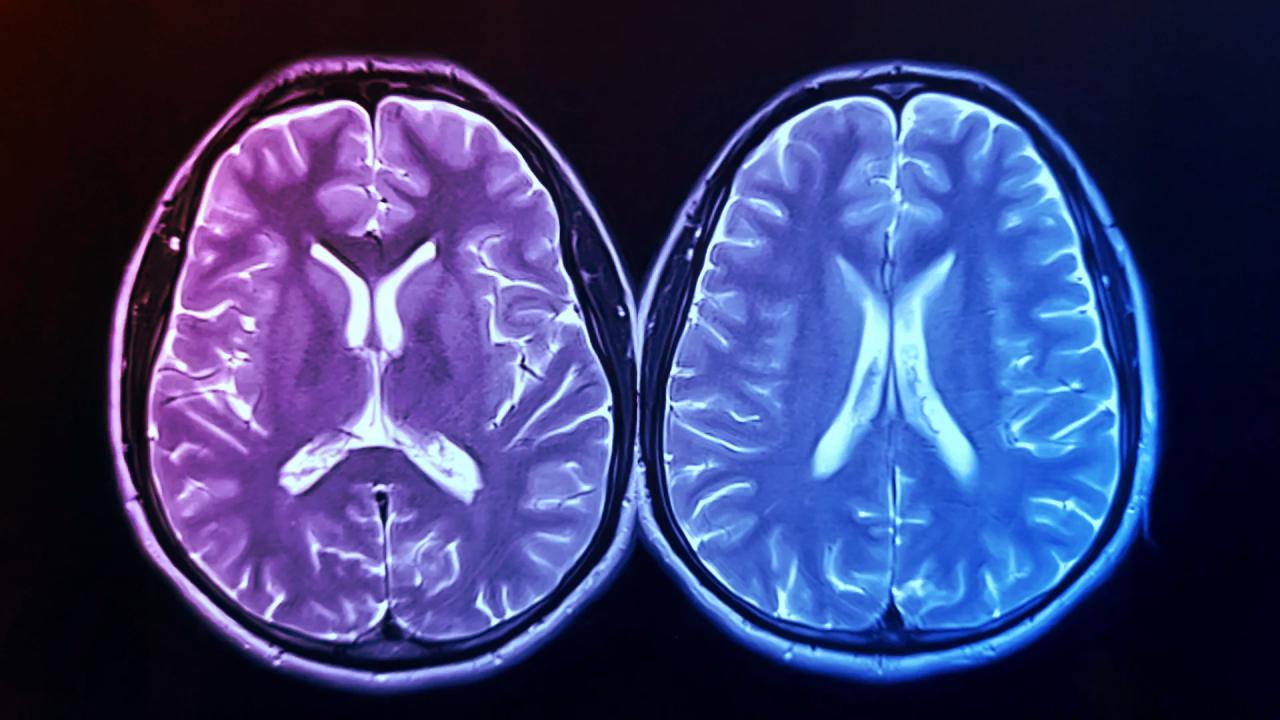

Így mérték az agy valódi korát

A résztvevők MRI-vizsgálaton estek át, így objektíven meg lehetett állapítani, hogy az agyuk megjelenése mennyire tér el a kronológiai életkoruktól. Az ilyen eltéréseket – angolul brain-PAD (brain predicted age difference), vagyis a becsült agykor és a kronológiai életkor különbségét – régóta összefüggésbe hozzák a fizikai és szellemi teljesítmény csökkenésével, illetve magasabb halálozási kockázattal. A vizsgálat végén az aktív csoport tagjainál átlagosan 0,6 évvel fiatalabbnak tűnt az agy, miközben a kontrollcsoportnál átlagosan 0,35 évvel öregebb lett, bár ez utóbbi eltérés statisztikailag nem volt jelentős. Ettől függetlenül a két csoport között majdnem egy teljes évnyi különbség adódott.

A 130 egészséges önkéntest két csoportra osztották: az egyik edzett, a másik maradt a hétköznapi életmódjánál. Az edzőcsoport heti kétszer hatvan percig edzett laboratóriumi felügyelet mellett, majd otthon is mozogtak, hogy elérjék a 150 perc/hét célkitűzést – az Amerikai Sportorvosi Kollégium elvárásainak megfelelően. Mérték az agy szerkezetét MRI-vel, a fizikai fittségüket pedig a VO2-csúcsérték alapján.